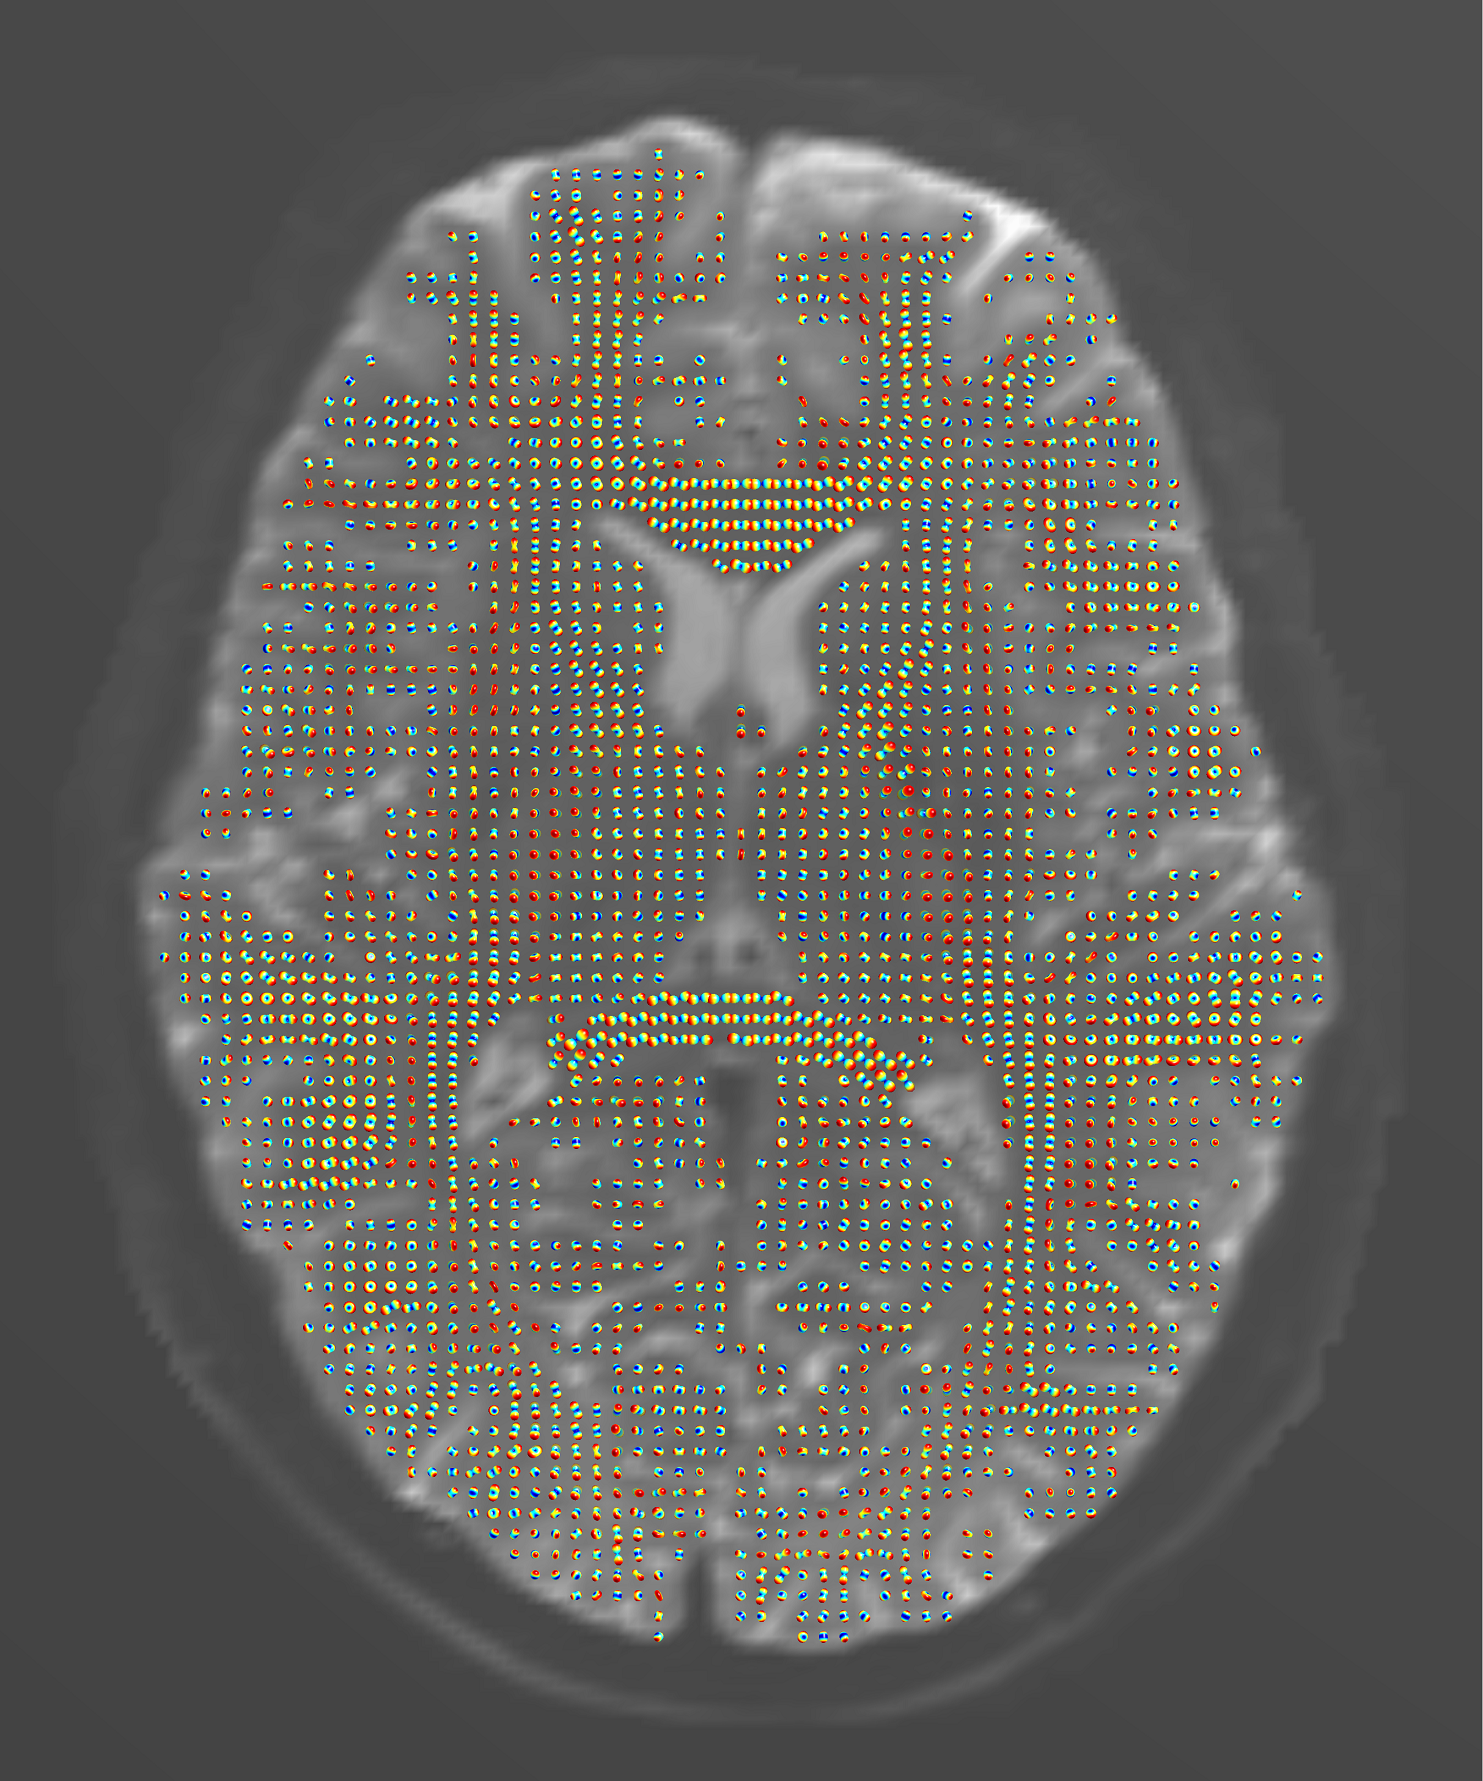

Figure 1. Orientation distribution functions (ODFs) reconstructed12 from the diffusion tensors of the HCP subject and visualized in the white-matter mask using the “CSA-ODF and Hough Tractography” Matlab toolbox13. The dataset contained images acquired at the 1.25 mm isotropic resolution along 270 diffusion gradient directions with b-values ranging from 990 to 3010 s/mm², in addition to 18 averaged b=0 images shown in the background, and the diffusion time of 40 ms.